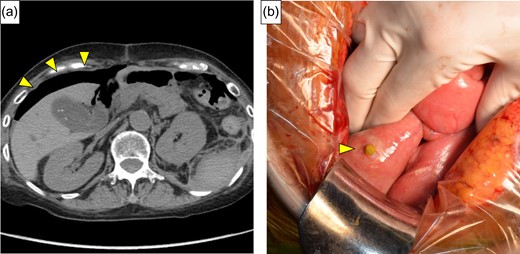

A 54-year-old woman was referred to our hospital because of abdominal pain. She had a history of adult Still’s disease at age 49 and underwent treatment with oral prednisolone, 90 mg/day and cyclosporine, 175 mg/day. A physical examination revealed deep tenderness in the abdomen. Laboratory data showed slight leukocytosis (white blood cell count 9100/μL) with a moderately elevated C-reactive protein level (9.3 mg/dL), while other data, including blood coagulation factor, were within normal ranges. Computed tomography (CT) revealed a small amount of extra-intestinal free air around the rectum and massive retroperitoneal emphysema between the rectum and the left kidney (Fig. 1a and b). Arterial aneurysm was not confirmed. Based on a preoperative diagnosis of rectal perforation, emergency laparotomy was performed, which confirmed peritoneal fluid collection (Fig. 2) and rectum perforation on the retroperitoneal side. After aspiration of the pus and irrigation of the area with saline, Hartmann’s operation was performed (Fig. 3a). Although she was undergoing immunosuppressive treatment, pathological study disclosed no association between diverticulum perforation and cytomegalovirus enteritis (Fig. 3b). On postoperative Day 4, she suffered a sudden intolerable left flank pain; her hemoglobin level was 7.5 g/dL, and slight prolongation of prothrombin time was recognized. CT revealed a left retroperitoneal hematoma and extravasation from the left first lumbar arteries (Fig. 4a). Emergency transarterial angiography and lumbar artery embolization was performed (Fig. 4b). On Day 20 after the first operation the patient felt a sudden right flank pain, and CT confirmed intra-abdominal free air (Fig. 5a). A second emergency laparotomy was performed, which revealed cecal perforation with no obvious masses (Fig. 5b). Perforation resulting from diverticulum was suspected, and an ileostomy without intraperitoneal anastomosis was performed because of concern about anastomotic leakage. Postoperatively the patient developed an intra-abdominal abscess, surgical site infection (Clavien-Dindo IIIa) and pneumonia (Clavien-Dindo II), which were treated conservatively. Although it took time to rehabilitate the patient and control the adult Still’s disease, she was discharged on Day 212 after the first operation. The patient is now doing well with comfortable activity of daily life.

(a) Contrast extravasation from lumbar artery and hematoma expansion lifting the left kidney was identified (yellow arrow). (b) Angiography revealed extravasation of contrast medium (red arrow) from the left first lumbar artery (yellow arrow).